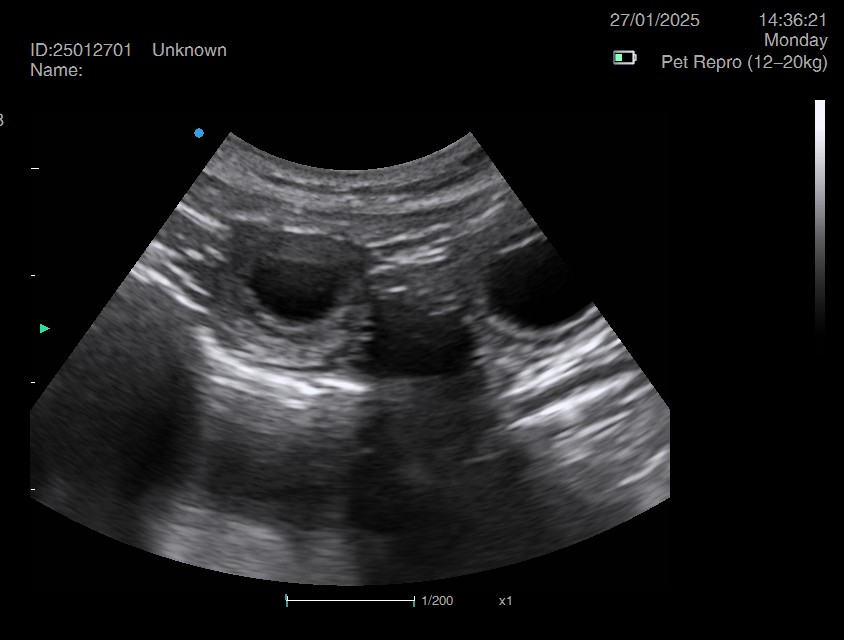

Pregnancy ultrasound scanning - Our pregnancy ultrasound service provides safe, non-invasive confirmation of pregnancy in both dogs and cats. Using advanced scanning technology and gentle handling techniques, we deliver clear, reliable results while prioritizing your pet’s comfort and wellbeing.Whether you visit our calm, home-based clinic or book a mobile appointment, we tailor each session to suit your pet’s needs—supporting responsible breeding with compassion, precision, and care.

Ultrasound pregnancy scanning is a safe, non-invasive way to confirm pregnancy in dogs and cats, offering breeders and pet owners peace of mind and vital information to support responsible care. It allows us to detect gestational sacs, assess foetal development, and estimate litter size—all while ensuring the wellbeing of the animal.

Pregnancy can sometimes be detected as early as Day 18 post-mating, but scanning at this stage is not routinely recommended. Embryos are still developing and may not be clearly visible, and there is a natural risk of embryo resorption, which can lead to misleading or inconclusive results.

For the most accurate and reliable scan, we advise booking between Day 25 and Day 32, when pregnancy is more easily confirmed and foetal structures are clearer. If an early scan is performed and no pregnancy is detected, we offer a FREE complimentary re-scan after 7 days at the clinic to ensure clarity and support informed decision-making.

Our approach balances early insight with ethical care—always prioritizing the comfort of the animal and the accuracy of the results.